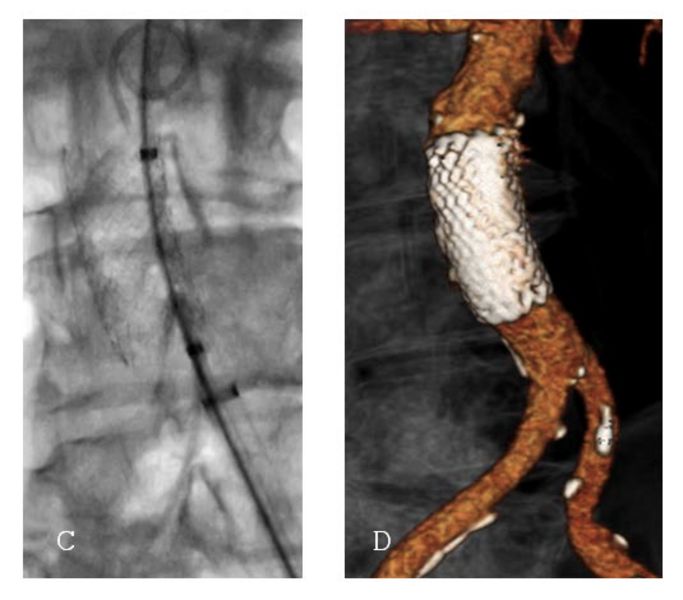

In der Studie wurden 260 Patientinnen und Patienten zwischen 2018 und 2022 behandelt. Das Durchschnittsalter betrug 74 Jahre, die Mehrheit war männlich. Bei rund drei Vierteln der Patientinnen und Patienten wurde das Aortenulkus zufällig entdeckt, bei einem Viertel hingegen aufgrund akuter Beschwerden wie Bauchschmerzen oder gar einer Ruptur diagnostiziert. Fast alle Patientinnen und Patienten erhielten eine endovaskuläre Therapie, also eine Behandlung über Katheter und Stentprothesen ohne Bauchschnitt. Nur einzelne mussten offen operiert werden.

Die Ergebnisse sind ermutigend: In über 99 % der Fälle konnte die Behandlung technisch erfolgreich abgeschlossen werden, und die Sterblichkeit innerhalb von 30 Tagen lag bei lediglich 1,5 %. Komplikationen waren selten und traten vor allem bei Patientinnen und Patienten auf, die wegen akuter Beschwerden oder einer Ruptur notfallmässig behandelt werden mussten. Begleiterkrankungen wie eine chronische Lungenerkrankung erhöhten ebenfalls das Risiko für Komplikationen.

Die Studie zeigt klar: Die endovaskuläre Versorgung stellt heute den Standard in der Behandlung infrarenaler Aortenulzera dar. Sie bietet eine sichere, schonende und wirksame Therapie – selbst bei komplexen Gefässveränderungen.